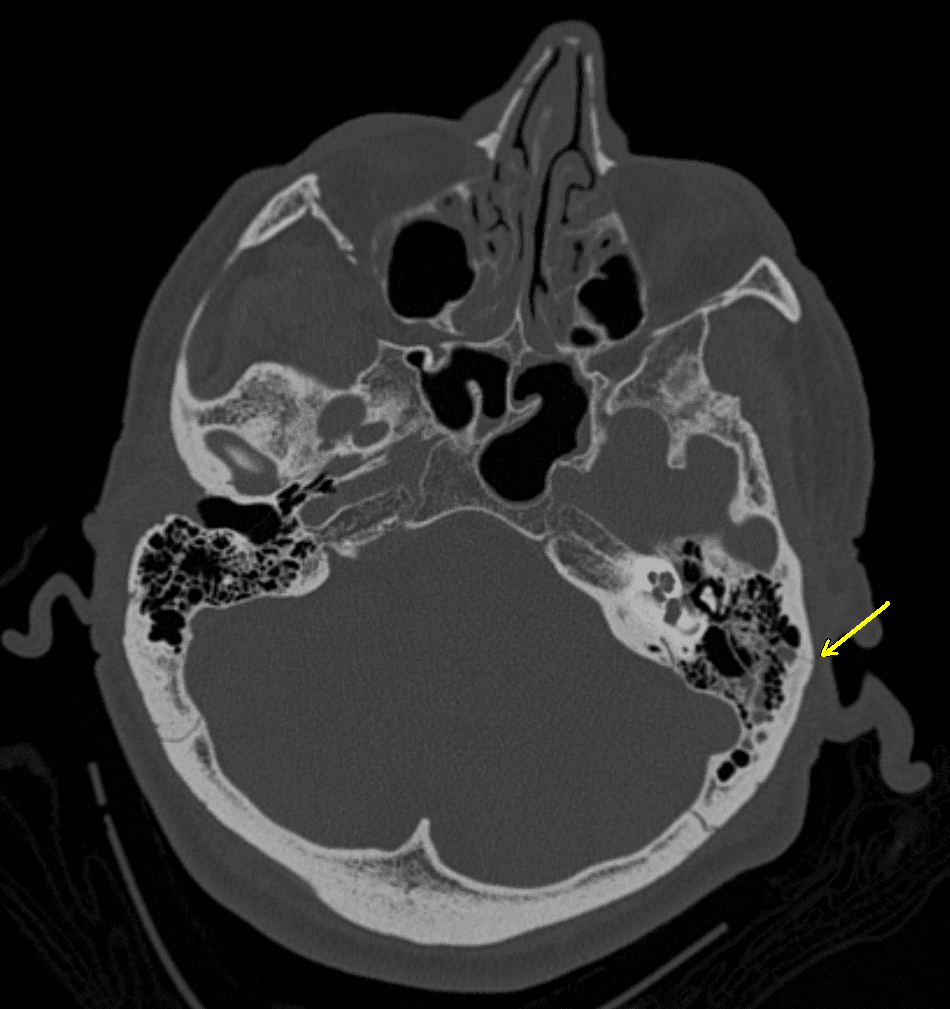

Basilar skull fracture